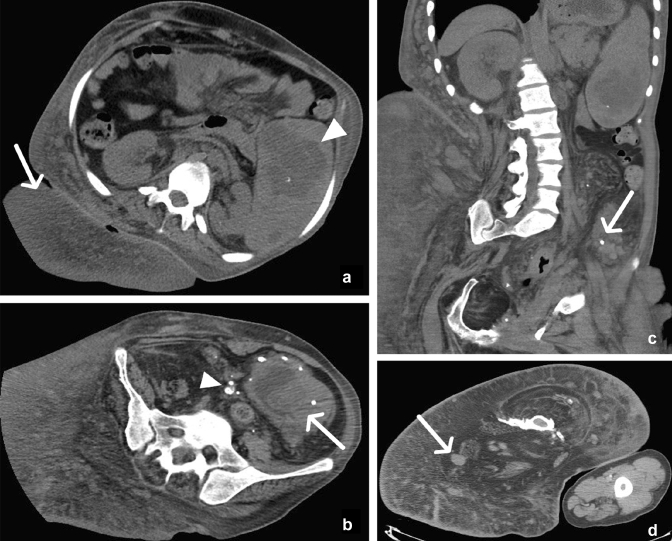

Fig. 19.

50-year-old female with a subcutaneous bone flap after decompressive craniotomy for a traumatic subdural hematoma. Axial (a), coronal (c), and sagittal (d) contrast-enhanced CT images demonstrate a curvilinear osseous structure (arrows) in the subcutaneous tissues of the right lower quadrant with surrounding hematoma and foci of gas (arrowheads). This corresponds to a missing fragment of the calvarium seen on axial head CT (b). In fact, the coronal suture can be seen on sagittal reconstructions (d) (arrow)